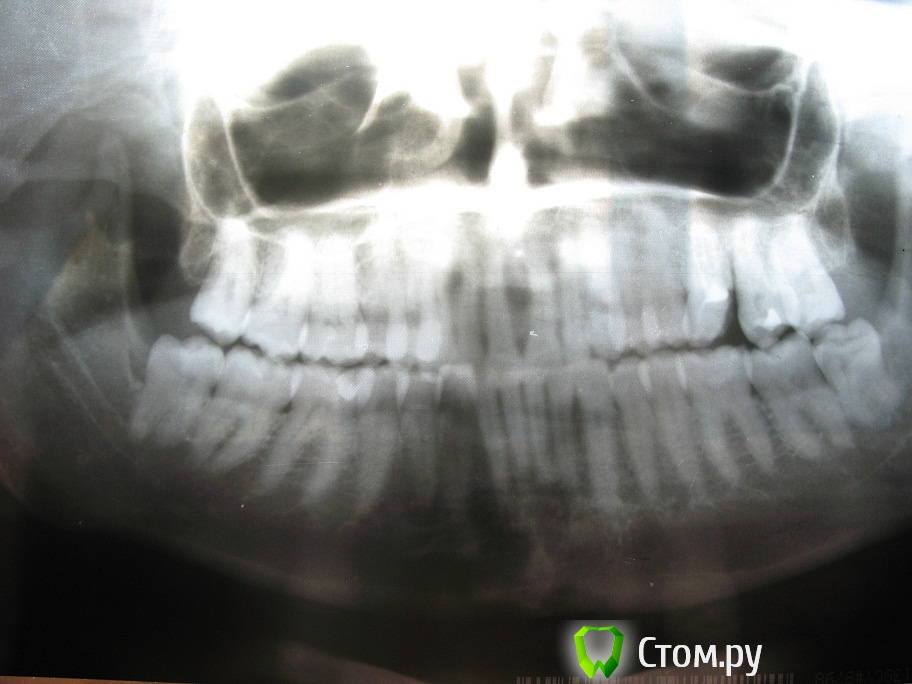

ylo99 Опубликовано 21 февраля, 2014 Поделиться Опубликовано 21 февраля, 2014 Здравствуйте ужаемые ортодонты!! очень нуждаюсь в помощи и в ваших советах.Мне 32 года. Живу в Москве.Прогрессирует стираемость нижних и верхних зубов ,(за последний год начали стераться и верхние зубы). Проблем с ВНЧС у меня нет, бруксизмом не страдаю. Нижняя челюсть недоразвита, ставила имплант в подбородок , чтобы как- то нормализовать профиль. Ассиметрия лица. Правый глаз расположен выше левого, а угол рта наоборот опущен вниз. Сами верхние зубы имеют наклон внутрь рта. Очень давно хочу решить эту проблему , но не знаю кого слушать . Сколько врачей столько и мнений. Одна сказала, вытягивать и верхние и нижние зубы. Другая- поднимать верхние вверх менять угол наклона . 3-я предожила насить каппу для постановки нижней челюсти в правильное положение , отправила к гнатологу, только потом брекеты. сегодня в цниисе, врач сказал, все зубы запротезировать у ортопеда -воостаносвить высоту, только потом брекеты.и челюстно лицевая операция . Мне нужен хороший специалист, которой за меня возьмется и до ведет дело до конца.Понятно что потребуется ортопед, но наверно после ношения брекетов. Уже не знаю к кому обращаться.Из снимков только ортопанограмма , 2 - летней давности. Ссылка на комментарий

Skip Опубликовано 4 марта, 2014 Поделиться Опубликовано 4 марта, 2014 У меня начались боли в шеи , голове, болит левый нижнечелюстной сустав . Куда бежать не знаю. Подскажите врача Ну вот, а говорили нет проблем с ВНЧС. Там, где Division II (резцы), всегда высокий риск развития дисфункции ВНЧС. Даже не знаю, кого Вам подсказать и куда бежать. Нижняя челюсть, действительно, короткая, но не смертельно. Хотя, учитывая симптоматику со стороны ВНЧС и ещё ряд проблем, всё это заставит доктора, который решится за Вас взяться, засучить рукава. Виртуально не могу сказать Вам ничего определённого, в отношении алгоритма лечения, т.к. для этого нужная непосредственная встреча, диагностика и пр. Предлагаемый Вам этап сплинт-терапии (капа, пишется с одним "П") будет неотъемлемой частью общего лечения, как собственно и полное протезирование в последующем. Ссылка на комментарий

Force Опубликовано 9 марта, 2014 Поделиться Опубликовано 9 марта, 2014 Лечение зависит от того, чего вы сами хотите. Каппа в терапевтическом положении позиционирует вашу нижнюю челюсть достаточно прилично вперед. Проблема в ретропозиции не только нижней, но и верхней челюстях. Вот и вопрос, чего вы сами хотите. Ссылка на комментарий